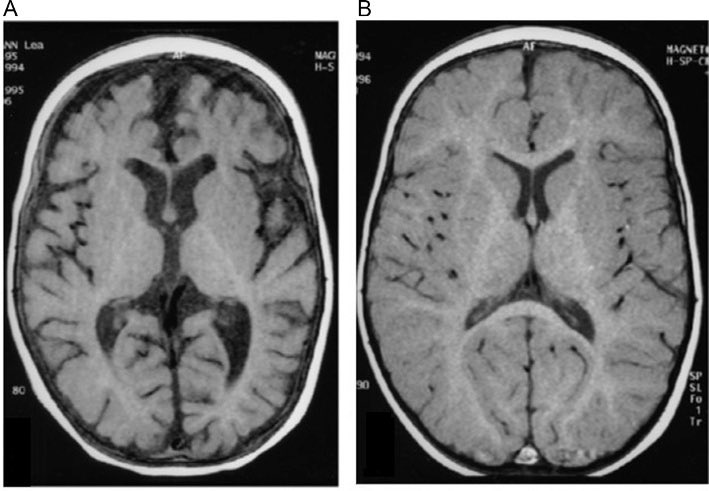

▫️Acute ischemic stroke 🌟🧠

✳️Axial CT of the brain demonstrate that the right MCA is hyperdense and there is loss of normal grey-white matter differentiation in the MCA territory

▫️ Acute ischemic stroke🌟🧠

3 days after the initial CT shows extensive bilateral MCA territory infarction and hypo attenuation

⏺Remember in the CT, The earliest finding of MCA occlusion is:

✳️hyperdense MCA sign ➡️

seen immediately and represents direct visualization of thrombus

✳️loss of grey-white matter differentiation ➕ hypoattenuation of deep nuclei

✳️cortical hypodensity ➕parenchymal swelling